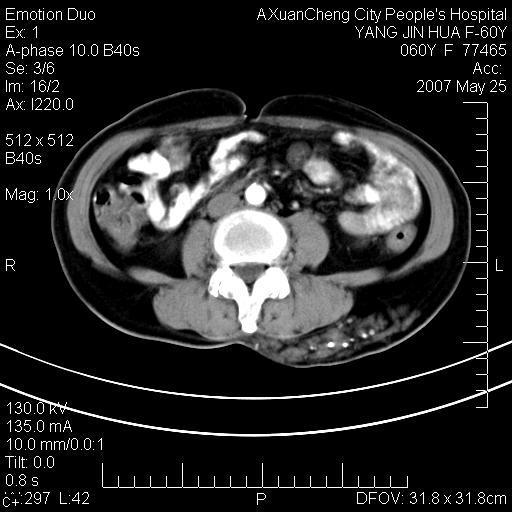

发现左侧腰背部包块40余年,逐渐长大,质软,局部表面可见扩张的血管影

左背部皮下良性肿瘤,密度不均,边界不清,内有脂肪、钙化,增强扫描无明显强化,血管平滑肌脂肪瘤?进一步诊断有困难,建议穿刺活检。

左侧背部皮下混杂密度肿块,结构较疏松,边缘欠光整,内有多发斑点状钙化,考虑:皮下血管瘤。

血管平滑肌脂肪瘤,支持!另应详细了解病史,待除外骨化性肌炎。

1.考虑左腰部皮下平滑肌脂肪瘤可能性大;

2.位置特殊,不除外畸胎瘤及错构瘤可能;

3.另骨化性肌炎应在考虑范围之内,请追问病史;

还是考虑皮下血管瘤,强化不明显可能跟大量血栓形成有关,好多战友考虑血管平滑肌脂肪瘤,血管平滑肌脂肪瘤的血管就不强化么?只要有血管就都应该强化。